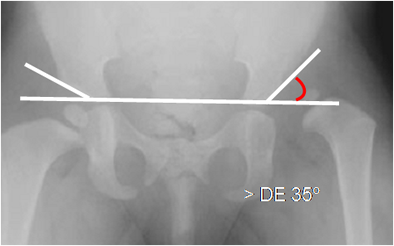

También se mide el ángulo acetabular, formado por la línea que une los cartílagos

tri-radiados y su intersección con otra, que pasa por el borde acetabular externo. En la displasia es mayor de 35º. (2). (Fig 37).

Fig 37. Displasia de cadera.

Rx AP. Aumento del ángulo acetabular izquierdo, por displasia.

Angulo derecho normal.